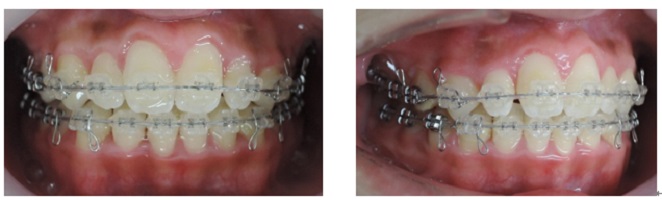

出来るだけ見えにくい矯正装置(ブラケット)を上下顎に装着して歯並びを整えていきます。矯正装置を装着後3日から7日ぐらいまでの間は歯が動きだすために軽い痛みを感じることがあります。

次にMEAW(マルチループ)を利用する事で咬み合わせの高さや前歯の傾斜を整えていきます。

また、MEAW(マルチループ)はゴムを24時間使用する事で最大の効果を発揮することが出来ます。

当院では簡易なMEAW(マルチループ)を使用する事で上下の前歯部をより綺麗な歯並びにしていきます。

この時にも24時間使用するゴムが大切です。